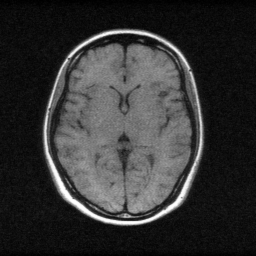

Reconstruction Gallery — 4 Scenes × 3 Scenarios

Method: CPU_baseline | Mismatch: nominal (nominal=True, perturbed=False)

Ground Truth

Reconstruction

Mean PSNR Across All Scenes

| Scene | I (PSNR) | I (SSIM) | II (PSNR) | II (SSIM) | III (PSNR) | III (SSIM) |

| scene_00 | 16.369188751529634 | 0.3769596313670564 | 28.91599361455386 | 0.8937325593738555 | 43.0888232643681 | 0.9970601105022431 |

| scene_01 | 17.02984109629589 | 0.5076141905187631 | 29.54697836453365 | 0.9088858192167282 | 44.00498178524224 | 0.9974331602373123 |

| scene_02 | 19.876634796830935 | 0.5132084125883123 | 29.296469693787934 | 0.8901788054246903 | 45.80916505985154 | 0.9983439806976319 |

| scene_03 | 16.209230008064964 | 0.3451008090497886 | 28.211197909256423 | 0.8836538261470794 | 42.81516446798818 | 0.997371546825409 |

| Mean | 17.371223663180356 | 0.4357207608809801 | 28.99265989553297 | 0.8941127525405883 | 43.929533644362515 | 0.9975521995656491 |